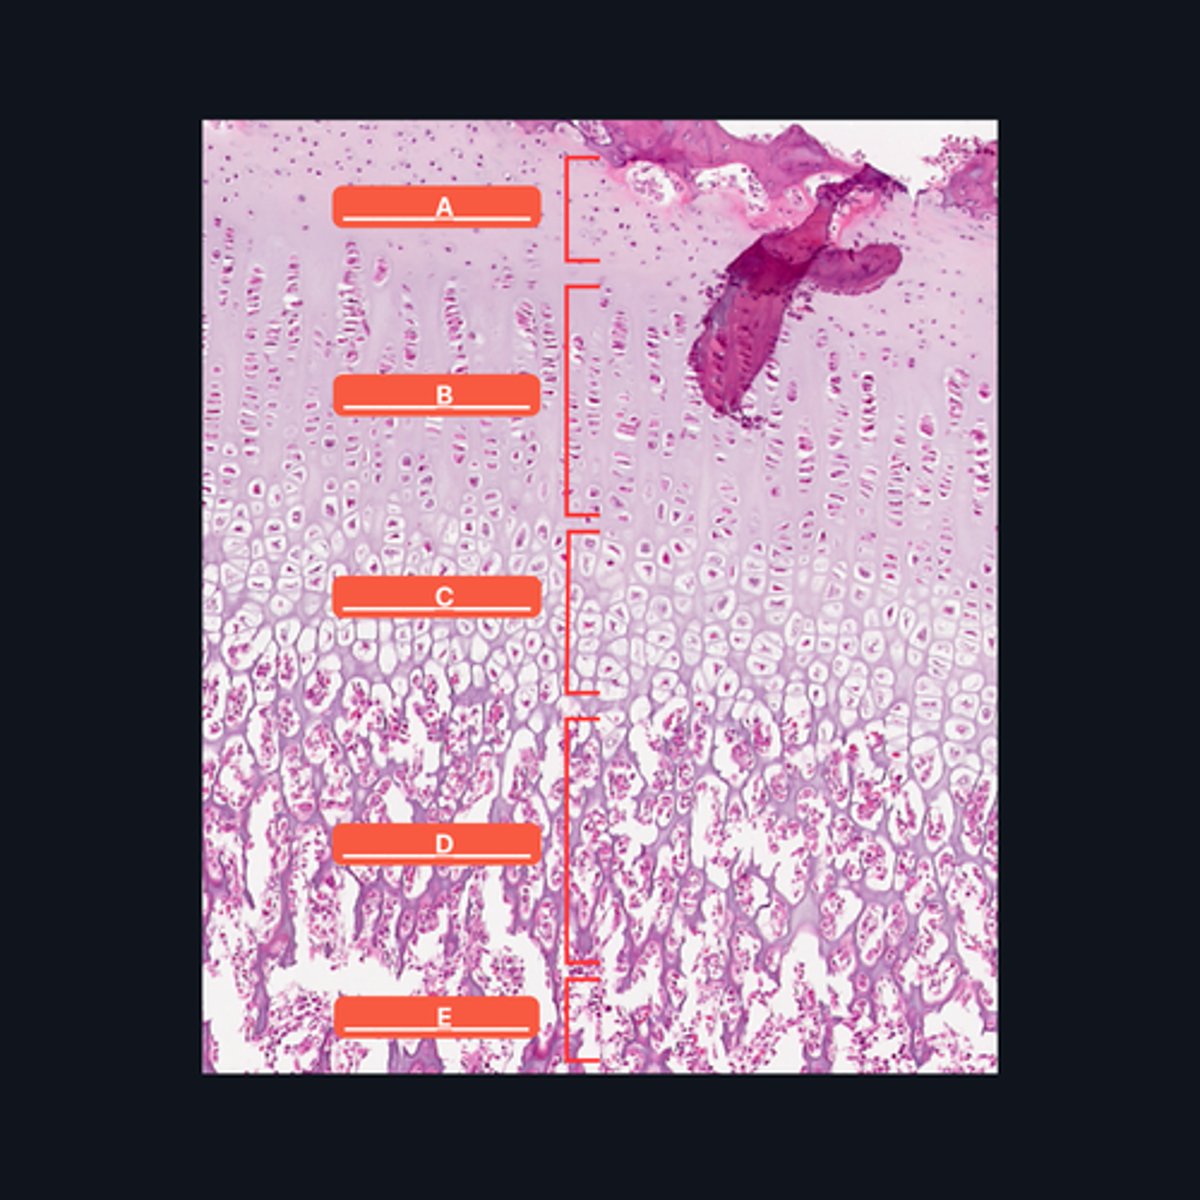

A - Zone of Resting Cartilage Cells

B - Zone of Proliferation

C - Zone of Maturation

D - Zone of Calcification

E - Zone of Ossification

Identify the pointed structures

B - Zone of Proliferation

Which pointed structure is the zone where instestitial growth occurs and what zone is it?

E - Zone of Ossification

Which pointed structure and what zone where many of the cavities left by cartilage cells merge to form marrow cavities?

C - Zone of Maturation

Which pointed structure and what zone do not divide anymore?

A - Zone of Resting Cartilage Cells

Which pointed structure and what zone anchors the epiphyseal plate to the epiphysis?

D - Zone of Calcification

Which pointed structure and what zone where the cartilage matrix is calcified